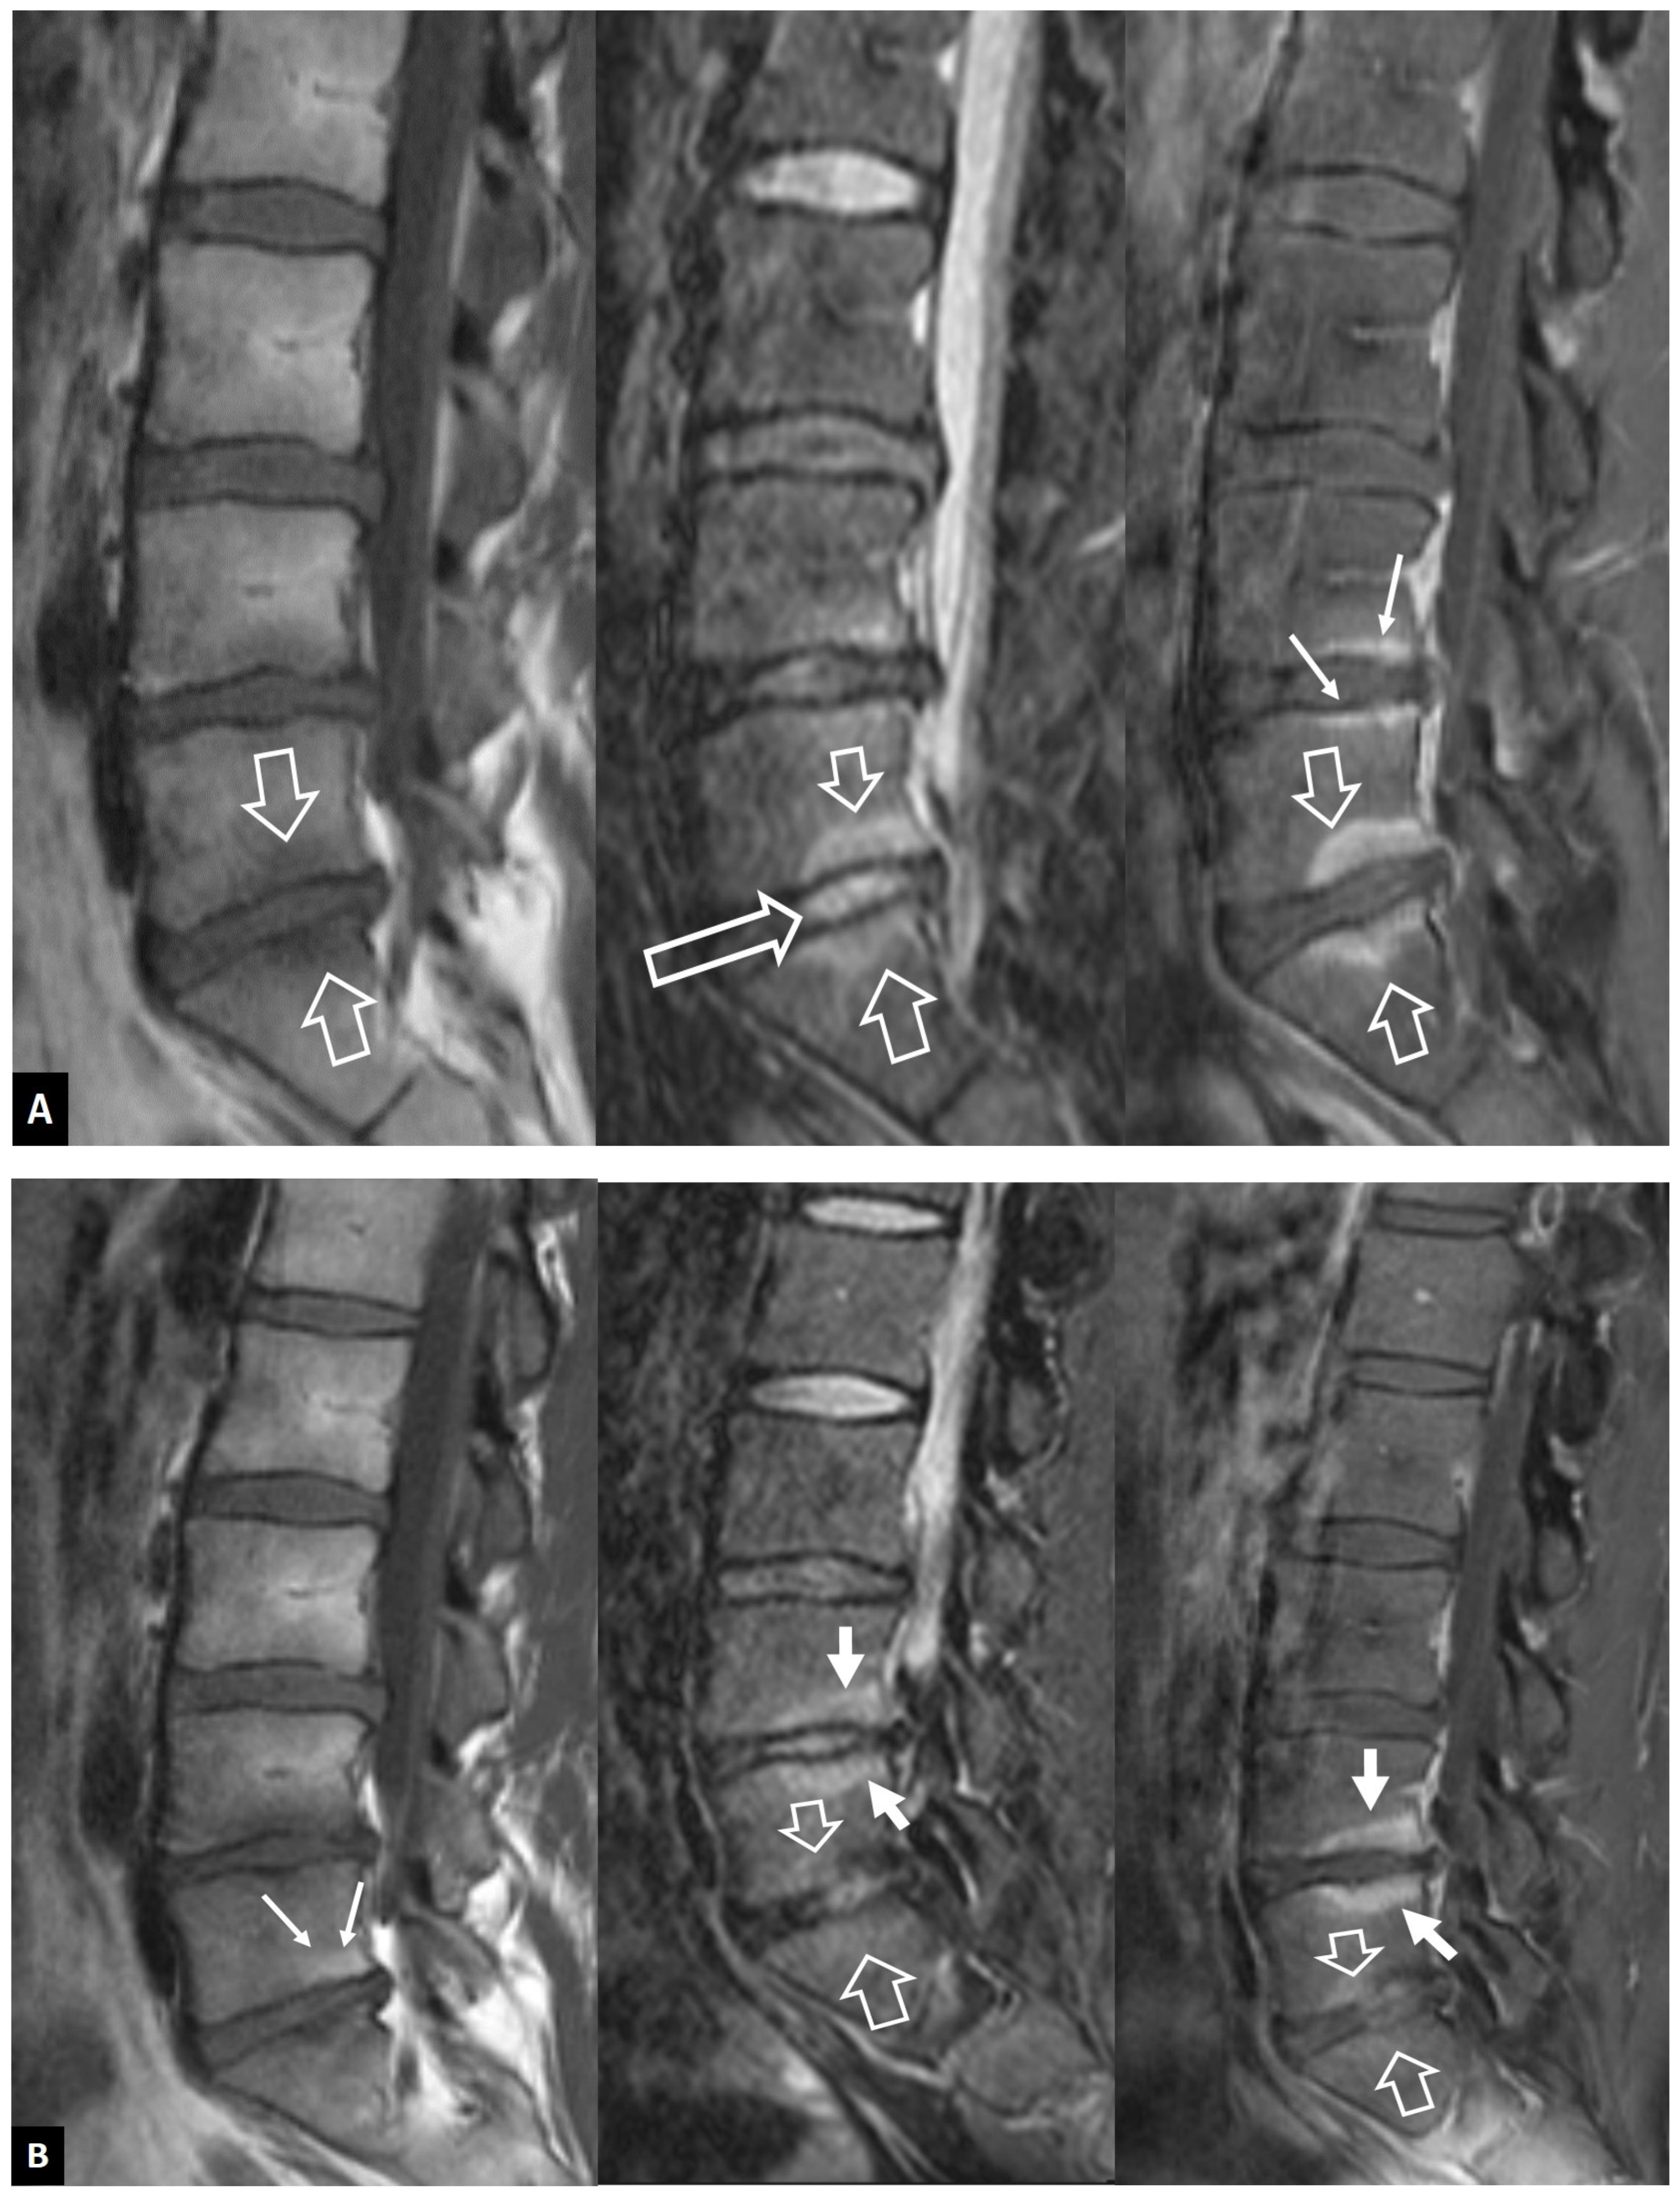

2.1.2. Aseptic Spondylodiscitis

2.1.3. SAPHO Syndrome

2.1.4. Destructive Spondyloarthropathy

2.1.5. Crystal Deposition

2.1.6. Post-Operative Aseptic Discitis